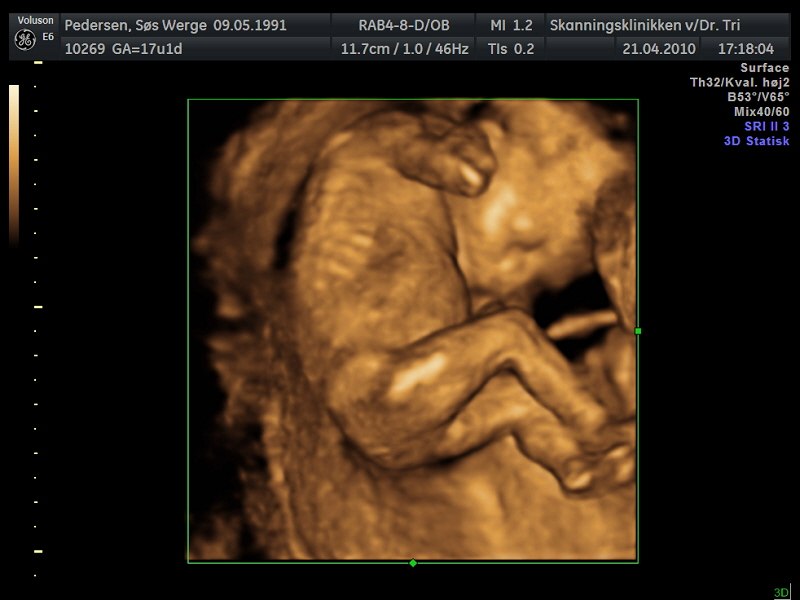

Billede 4 :Gennemscanning